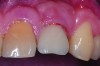

Fig 1. Clinical view of maxillary left lateral incisor implant in a healthy 48-year-old man. The swelling in the tissue surrounding this implant also bled on probing with depths up to 8 mm and exhibited purulence. The implant has been present for 14 years.

Figure 1